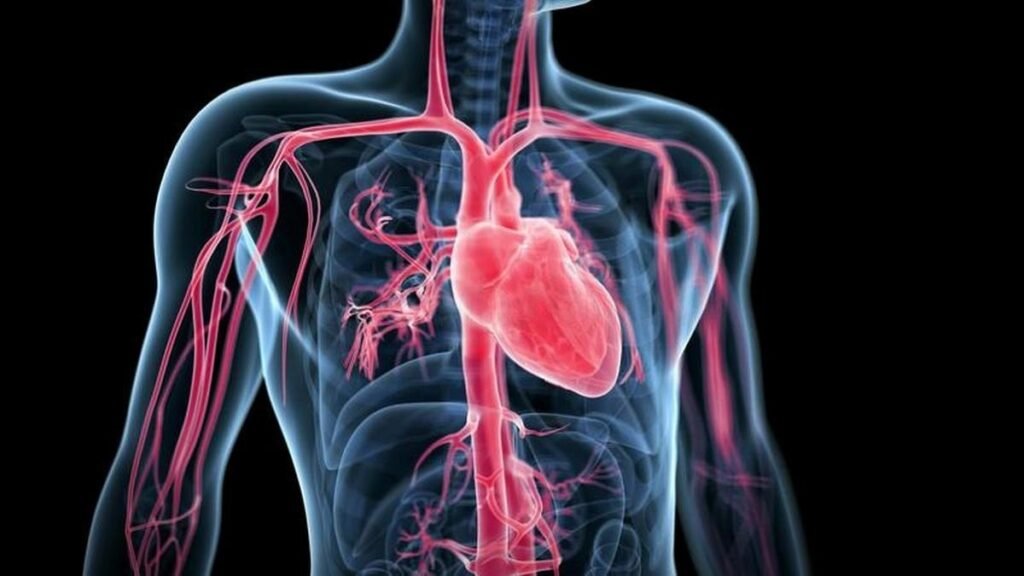

Digital illustration of a human chest with highlighted heart and blood vessels, showcasing expert Angiography in Indore by Dr. Akhilesh Jain.

Angiography is a minimally invasive imaging test that helps visualize the blood vessels of the heart. It identifies blockages or narrowing in the coronary arteries the arteries that supply blood to your heart muscles.

During Angiography in Indore, a special dye (contrast agent) is injected into the blood vessels through a thin, flexible tube called a catheter. The dye makes the blood vessels visible on X-ray images, allowing doctors to see if blood flow is restricted.